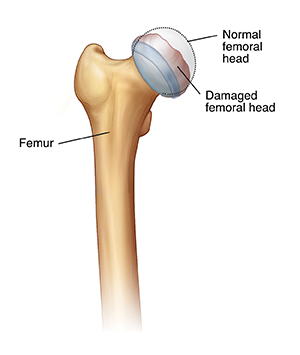

Your child has been diagnosed with Legg-Calvé-Perthes (LCP) disease. It is a problem with the head of the thighbone (femoral head). The femoral head is the ball-like part of the bone that fits into the hip socket. With LCP disease, the blood supply to the femoral head stops. The reason for this is unknown. As a result, the femoral head becomes weak, and a portion of it dies (avascular necrosis).

| In a normal hip joint, the femoral head is smooth and round. |

| With LCP disease, the femoral head is damaged and loses its normal shape. |